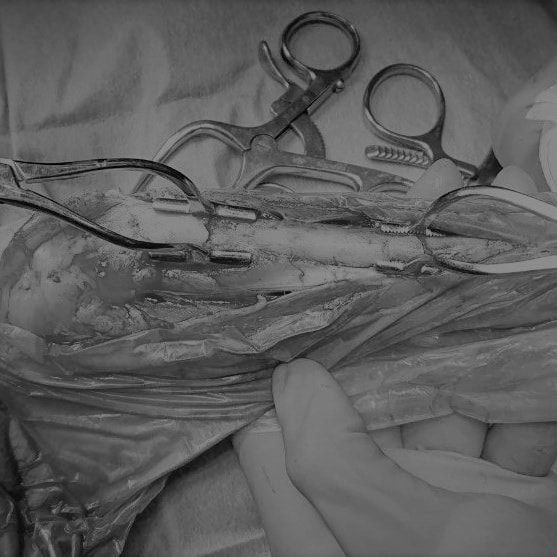

Advanced Locking plate system と Locking compression plate system

当院ではAdvanced Locking plate system(ALPS)と、Locking compression plate system(LCPS)という骨接合法で骨折症例の治療を行っています。

Advanced Locking Plate System

従来型のプレートのように広い面積で骨と接するプレートを用いて固定を行った場合、プレート下の骨はプレートとの接触面において血行が絶たれ壊死し、それがリモデリングされると骨密度が低下する。この骨密度の低下防ぐために、骨折部局所への血行を温存することの重要性が近年改めて認識されるようになってきている。Advaed Locking Plate System (ALPS)は従来型のプレートシステムの欠点を改良し、より使いやすく、より骨への血行を阻害しないようにというコンセプトで作られた。

Advanced Locking Plate System の特徴

- 骨への血行障害は最小限である

- 上下左右にベンディング可能でより3次元的な成形が可能

- すべての部位においてプレート強度は均一である

- ロッキングスクリューと圧着型スクリュー(皮質骨スクリュー)の双方が使用できる

- ダイナミックコンプレッション機能

- 生体親和性の高いチタン製

- トイ犬種から馬まで応用できるサイズ展開がある

Locking Compression Plate

LCPは、スクリュー(ネジ)とプレート(金属の板)をロックする特殊な構造により骨折部位を固定する新しい世代のプレートシステムです。ひとつのホールでロッキングスクリューとスタンダードスクリューの使用を選択できるユニークな構造をしているため、骨折断端間の圧迫を目的とした従来型プレート固定法に加え、高い角度安定性を有するロッキングスクリューを用いた固定法の選択が可能です。従来のプレートシステムでは困難だった部分の骨折や癒合不全の症例に高い治療効果をもたらします。

脊髄の減圧、脊柱管の再構築・安定化を目的に、片側椎弓切除術およびMatrixMANDIBLE Plateによる椎体固定を実施しました。

隣接椎体を架橋するようにプレートを設置しました。

Arthrex社のターゲティングデバイスを用いてピンニングの位置を調整することで、確実な固定を行っています。当院ではこの手術器具以外にも、人の手術にも使用される様々な器具を導入し、手術精度を高め、また医療メーカーと新しい器具の開発、試作にも取り組んでおります。